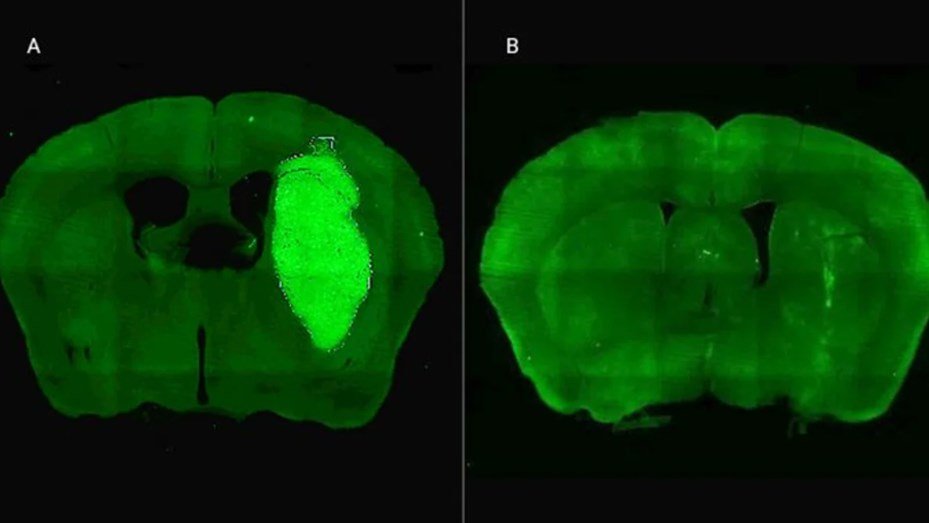

Además, P60 tuvo efectos antitumorales directos, reduciendo la viabilidad y la migración de las células de glioblastoma e inhibiendo la proliferación de células endoteliales que son clave para la progresión del tumor. Para evaluar estos efectos, los autores del estudio utilizaron una variedad de modelos celulares murinos (de roedor) y humanos. “En particular, los cultivos derivados de biopsias de pacientes con glioblastoma desarrollados por nuestro colaborador Guillermo Videla Richardson, del Instituto FLENI, son muy útiles para representar la heterogeneidad de estos tumores”, indicó Candolfi.